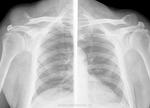

+1. Подагрический полиартрит 4ст.

Интереснейший случай был выставлен Татьяной Валентиновной

Наблюдение Татьяны Валентиновны

Так вот,инвалидом он является по псориатическому полиартриту.

Не поверите,но я сам читал диагноз в направлении.Вмешиваться не стал,не в моей поликлинике дело было,просто снимки "стырил".

Первый раз подагрический артрит с таким размахм вижу...

Мне вспомнилось слово мутилирующий.

Изначально подумала на ревматоид, если честно.